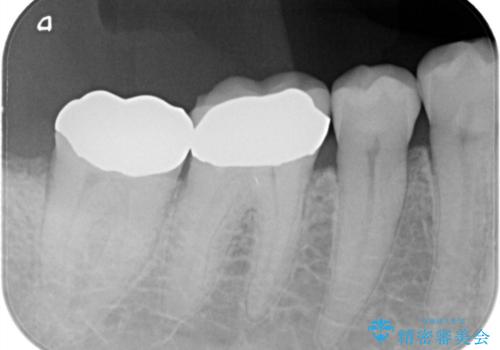

- 奥歯の詰め物が取れたことを主訴に来院されました。

噛む力が非常に強いため、破折しづらいゴールドクラウンにて修復治療を行なっています。

咬合力の強い患者さんに対してはセラミッククラウンでは破折リスクが高いためゴールドクラウンが適しています。